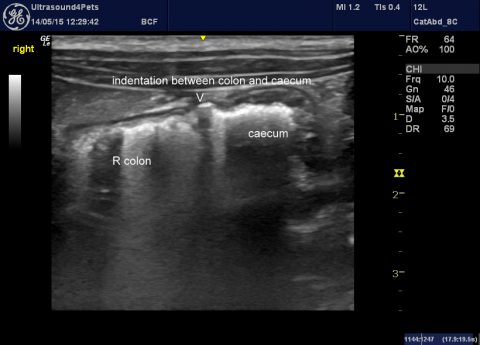

Ultrasonography of pneumothorax

Ultrasonography is surprisingly good as a rapid, readily available imaging modality for screening potential pneumothorax patients. Since cardiogenic pulmonary oedema, pulmonary thromboemboli, pneumonia, pleural effusions and intrathoracic neoplasia can also be detected it’s a powerful tool. The technique can be mastered by anyone with a few minutes to spare. Apply a micro-convex probe to the … Continue reading